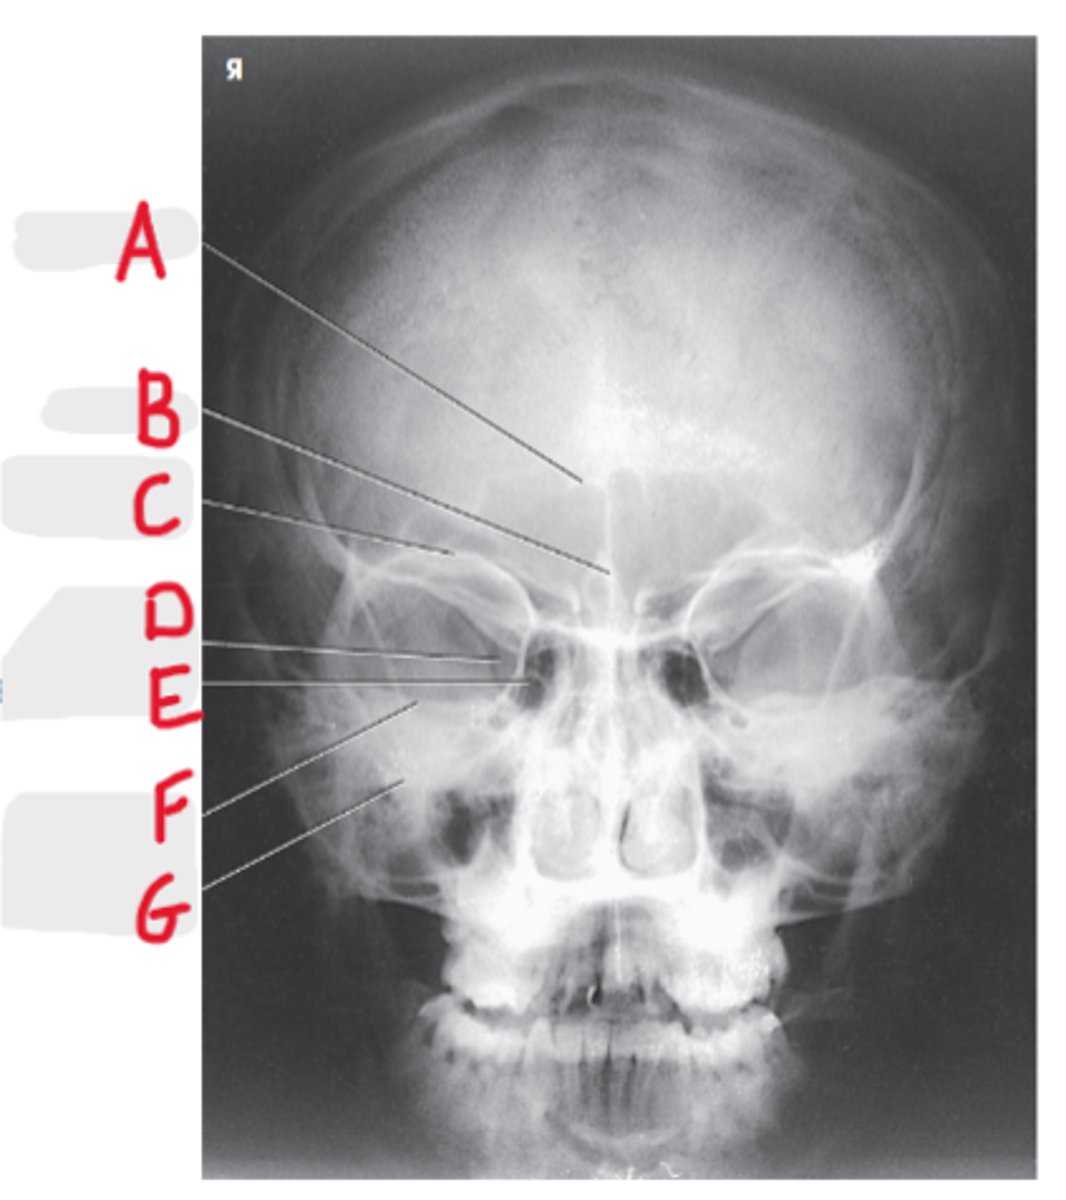

Maxillary sinus

A

Ethmoid air cells

B

Mandible

C

Sphenoid Sinus

D

Foramen spinosum

E

Mandibular condyle

F

Dens or odontoid process

G

Petrosa

H

Mastoid process

I

Occipital bone

J

Parietoacanthial (Waters Method)

What projection is this?

CR to exit at acanthion

What is the CR for the Parietoacanthial (Waters Method)?

MML perpendicular to IR

What line should be perpendicular to the IR on a Parietoacanthial (Waters Method)?

Maxillary Sinuses

What sinuses are best demonstrated on the Parietoacanthial (Waters Method)?

37 degree angle from IR plane

What angle should the OML be at for a Parietoacanthial (Waters Method)?

Equidistant lateral border of skull and lateral borders of the orbits

How do we look for rotation/tilt for the PA Caldwell or Waters?

Pretrous ridges lie inferior to maxillary floor

Where do the petrous ridges (pyramids) lie on a Waters radiograph?